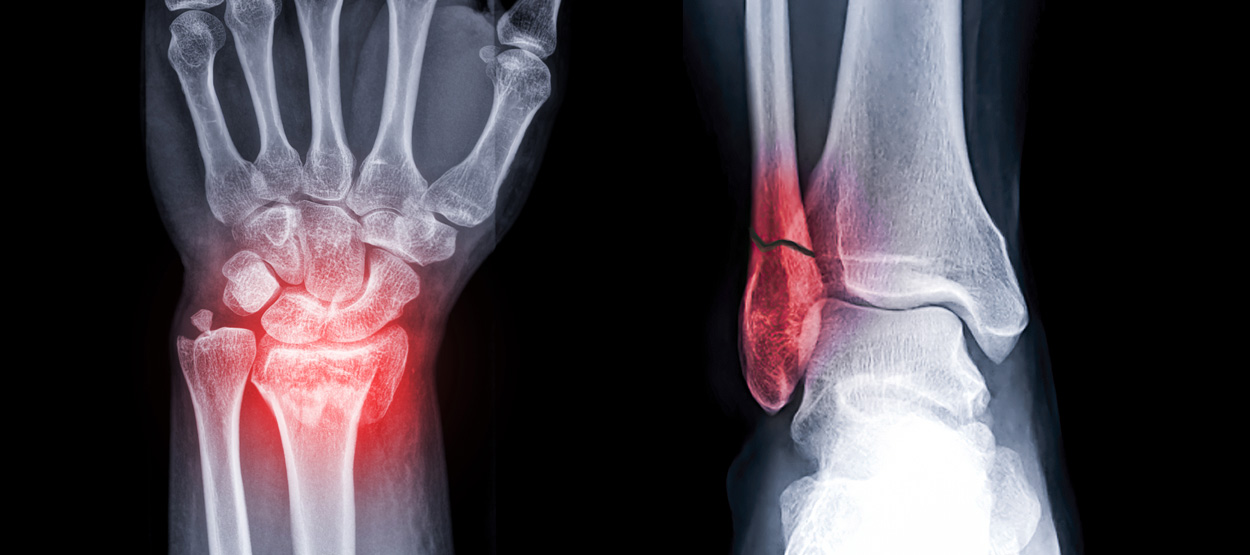

골절이 심하지 않은 경우에는 깁스로 고정해서 유합을 시킬 수 있으나, 정도가 심한 경우에는 손,발목 골절 수술을 진행할 수 있습니다.

뼈에 금이 가거나 부러진 상태를 말합니다. 외부 충격, 낙상, 교통사고 등 다양한 원인으로 발생할 수 있으며,

모든 연령대에서 발생 가능하지만 특히 어린이와 노인에게서 흔하게 발생합니다.

손목 골절